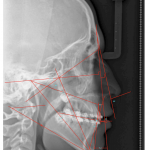

- Jarabak